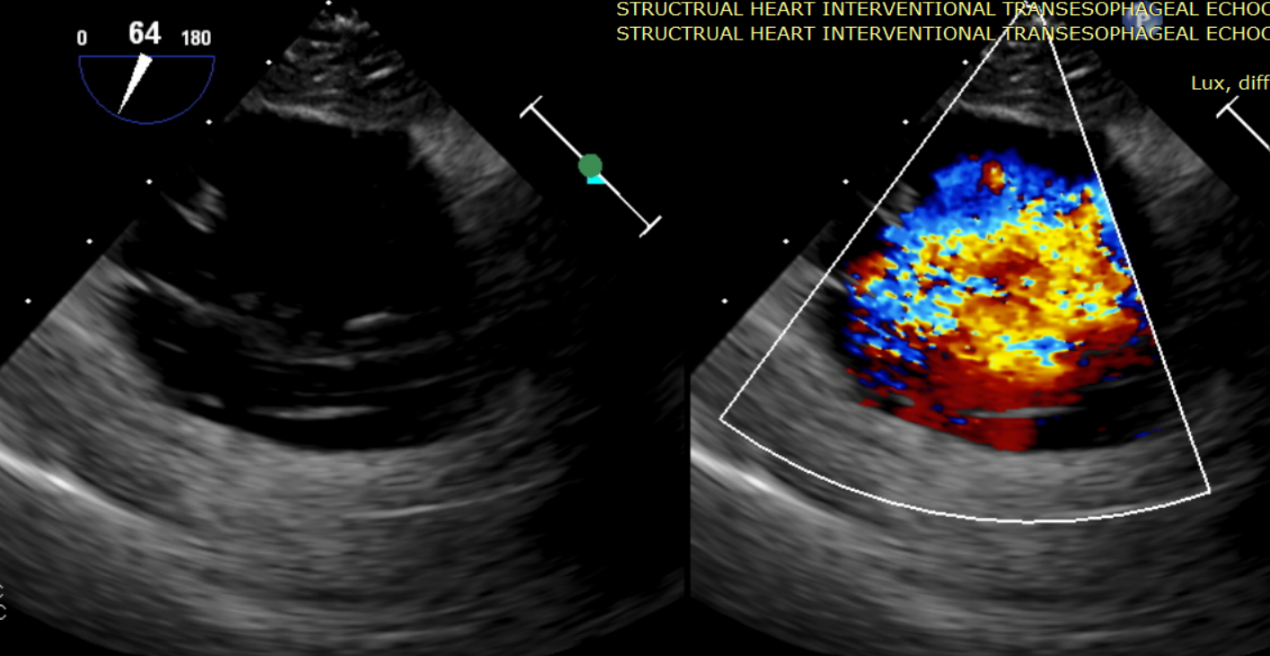

術(shù)前超聲提示大量三尖瓣反流

術(shù)中輸送器在超聲引導(dǎo)下調(diào)整位置

術(shù)后超聲提示無瓣周漏